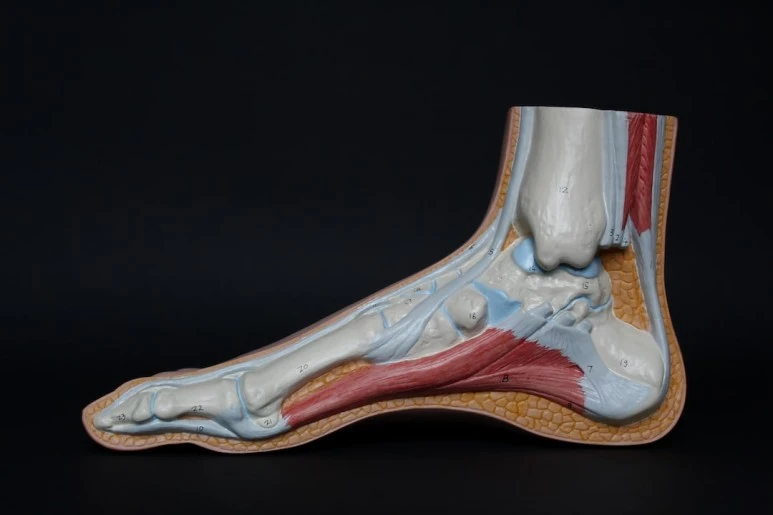

아이가 앉고 의사는 다치 왼쪽 다리를 구석구석 만져보았다. 아킬레스건 뒤쪽을 누르니 "아!" 하며 아이는 짧은 고함질렀다.

"아킬레스 건염입니다."

지난달부터 아이는 학교에서 농구를 배우기 시작했는데 농구하고 온 날은 항상 피곤해서 바로 자곤 한 기억이 났다. 당분간 운동은 하지 말고 점프하는 행동이 들어가는 운동은 하지 말라고 했다. 특히 줄넘기는 최악이라며 절대 하지 말라고 했다. 또한 많이 서 있거나 걷기, 살찌는 것을 조심하라고 했다.

앞으로 한 달 동안 운동은 하지 말라고 당부하셨다. 이때 잘 쉬어주지 않고 운동을 계속하면 아킬레스건이 파열될 수 있다고 경고하셨다. 아이가 어려 약은 먹지 말고 저절로 나아지도록 하고 2주 후에도 아프면 그때 다시 오라 했다. 아킬레스건 파열이라는 단어에 두려움이 엄습했는지 두려워했다.